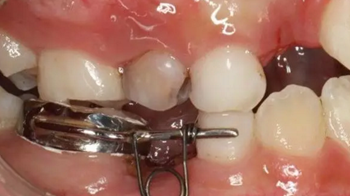

42、牙面拋光,試合制作好的間隙恢復(fù)器,將曲簧水平部分形成與牙面弧形一致,羧酸鋅水門汀粘結(jié)固定

43、粘結(jié)后的頰面觀

44、8周后復(fù)診間隙推開,自動(dòng)變換為間隙保持器